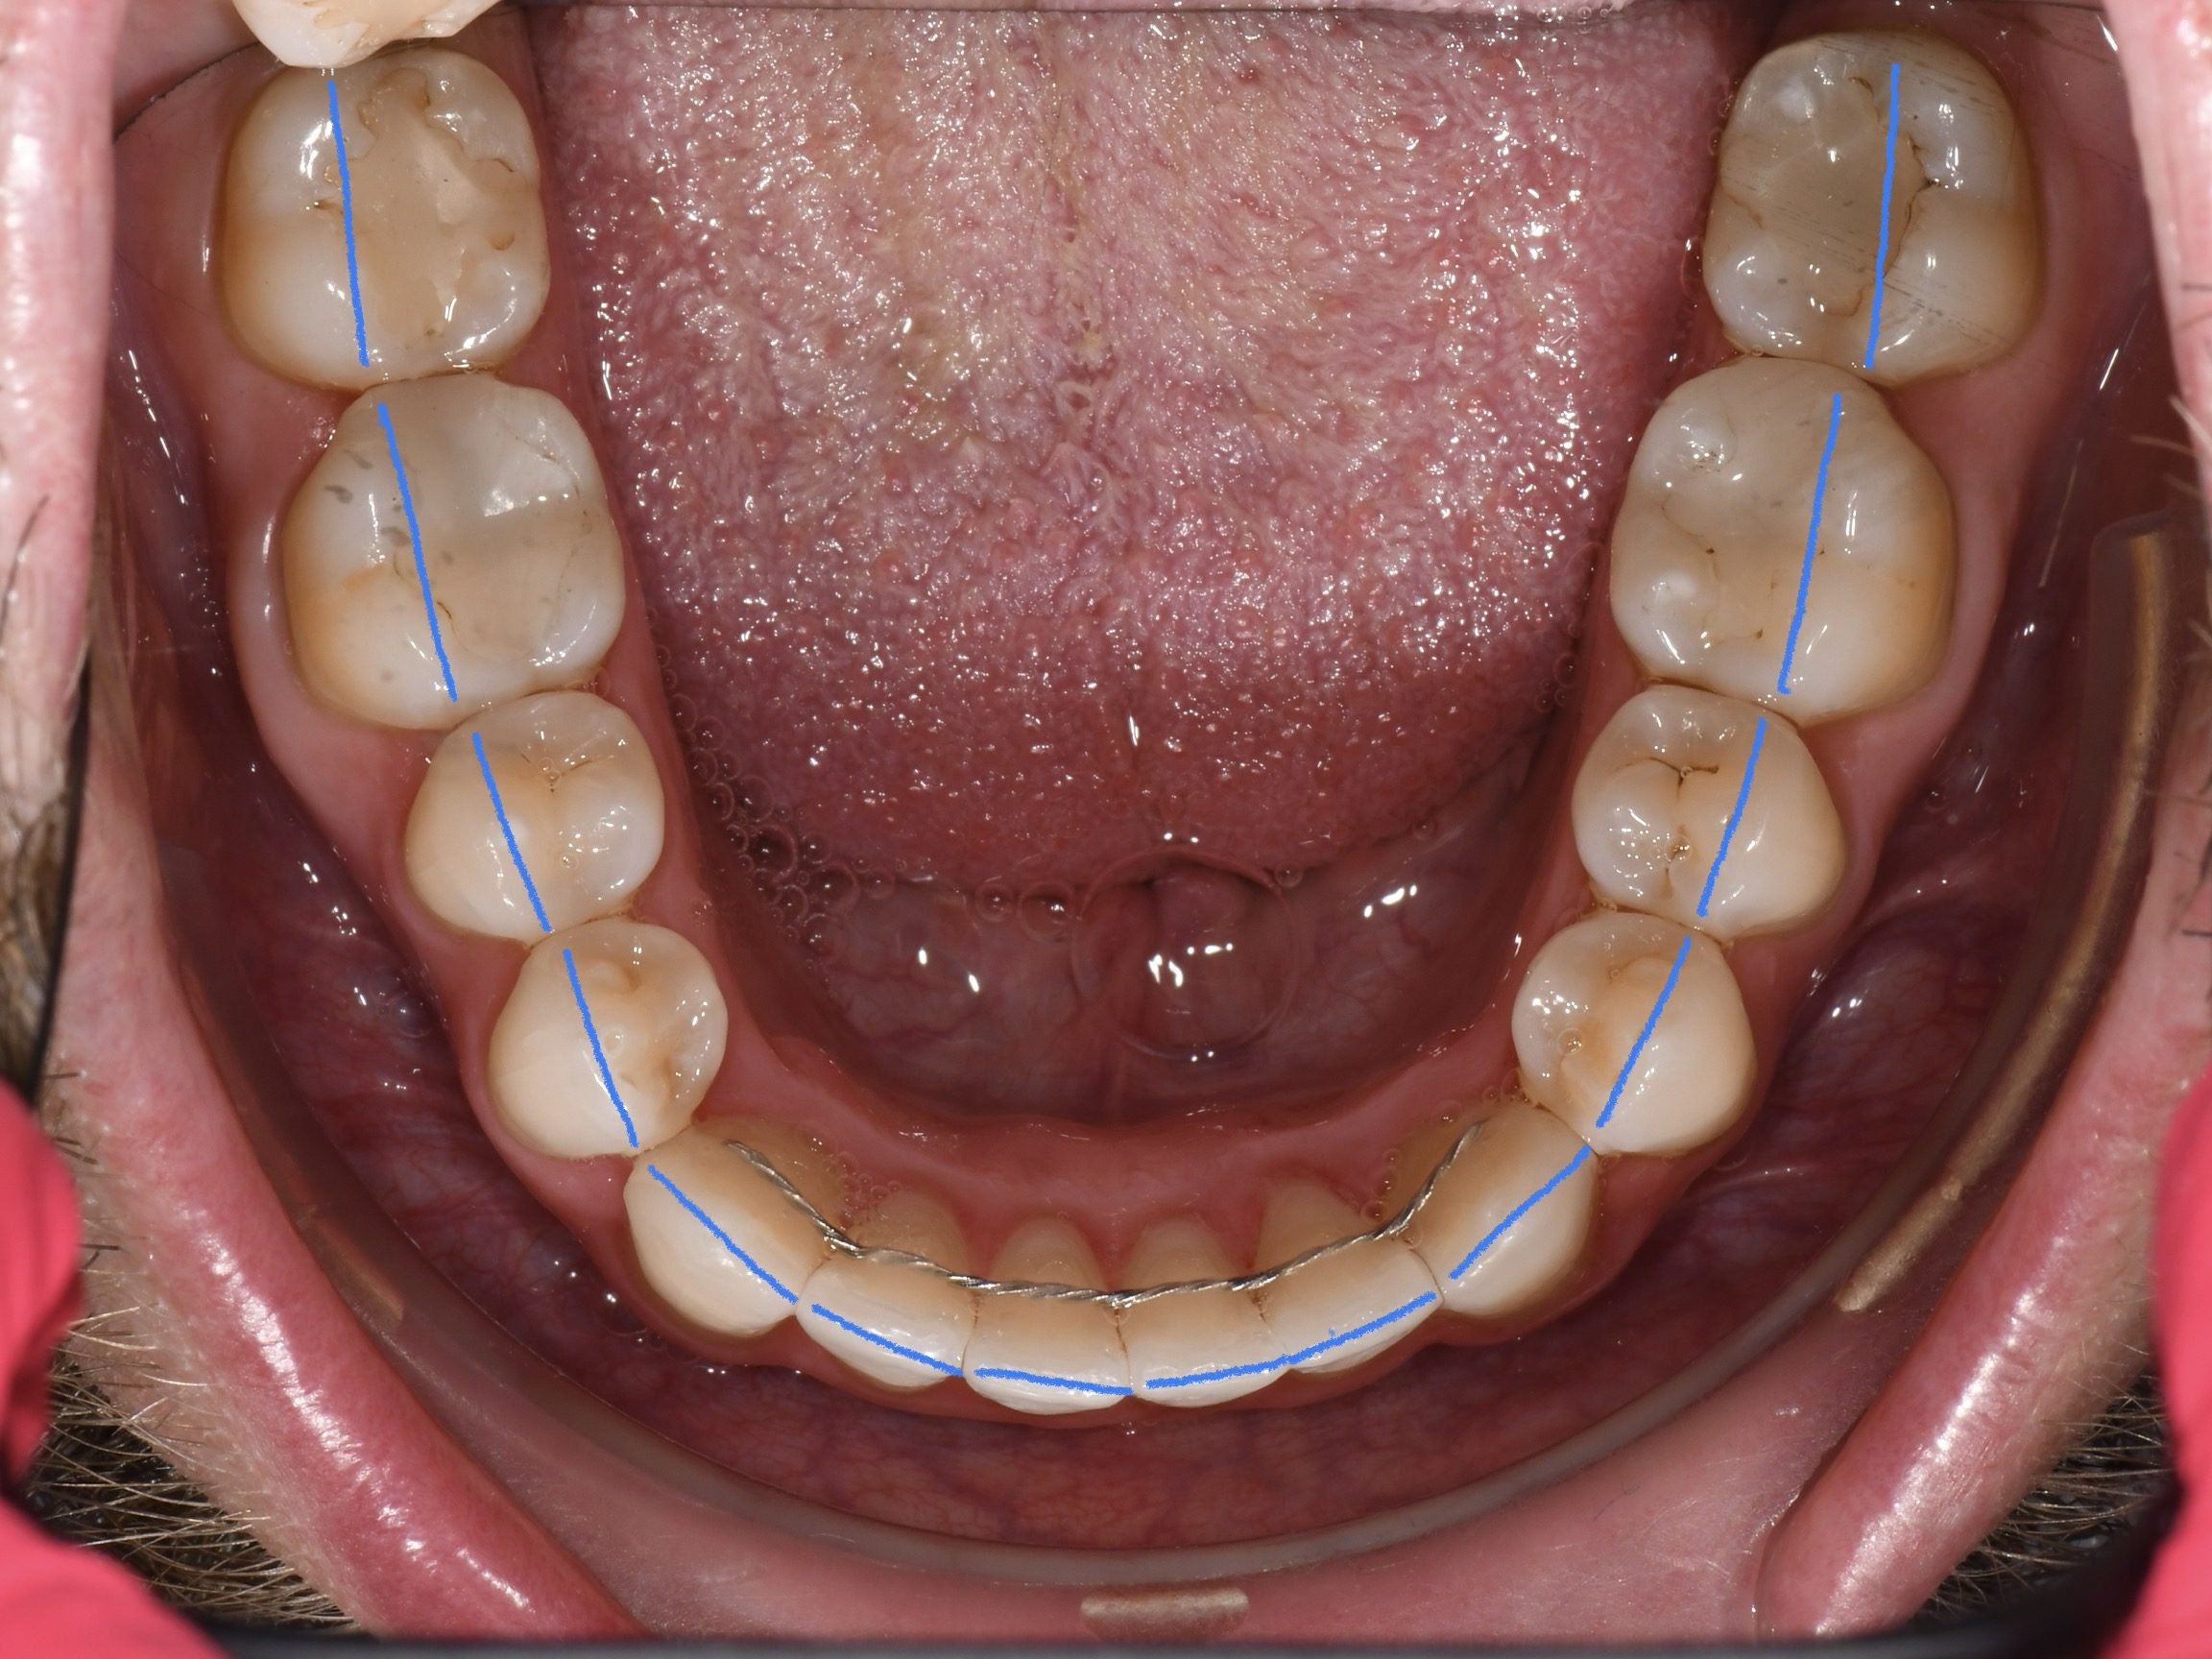

Az elmúlt évekből rengeteg szakmai referenciát tudnánk bemutatni, amelyek különböző fogszabályozási problémákat oldottak meg. Válogatva a több száz esetből, ezen az oldalon olyan képeket, információkat igyekeztünk bemutatni, amelyeknek a segítségével a jövőbeni pácienseinknek azt tudjuk üzenni: A Te fogsorod is lehet gyönyörű!